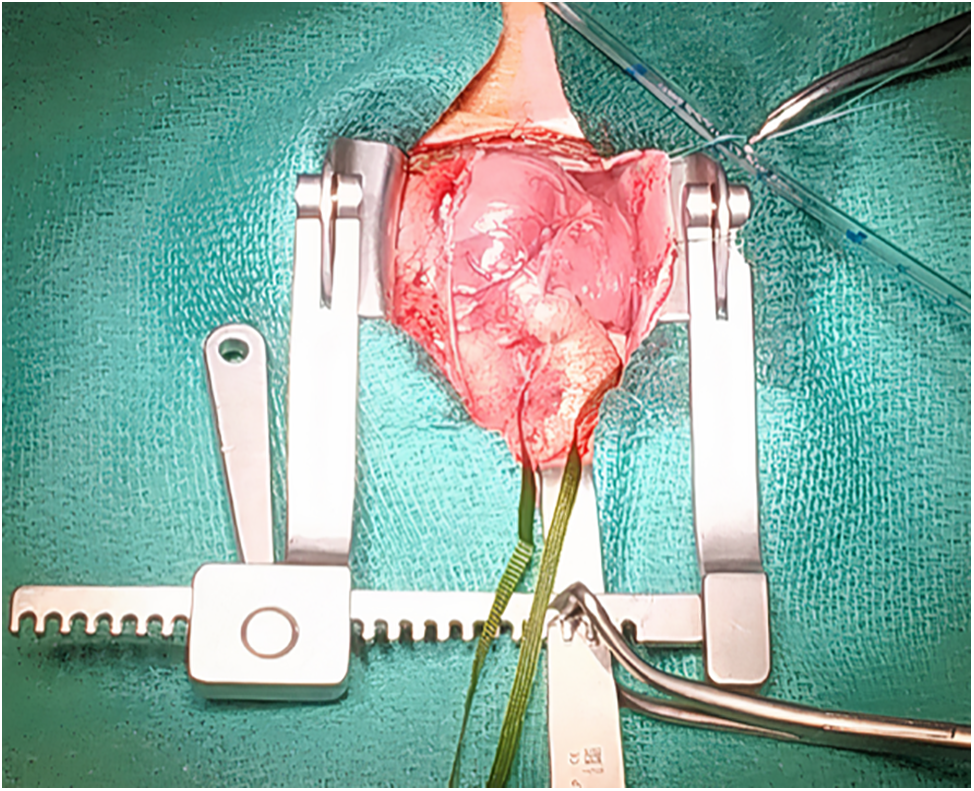

Emergency surgery was done on the 2nd day of life for left ventricle dysfunction. After median sternotomy, we could see the aneurysmal dilatation at the site of the tunnel at the aortic root anteriorly, with small RCA (Fig. 2) and a PDA which we closed with a clip. After cardiopulmonary bypass, cross-clamping, and opening the aorta, we used selective cardioplegia first in the LCA then the RCA was very difficult to access as the ostium was very small, we could canulate it after multiple trials. We found a bicuspid aortic valve, AVT which we closed by bovine pericardial patch with 6.0 prolene below the level of the facing right coronary ostium. After the closure of the aorta and removal of the clamp, the heart started beating spontaneously in a sinus rhythm. Weaning off bypass was smooth under a small dose of adrenaline and milrinone. The transesophageal echocardiography revealed no dyskinesia, no gradient over the mitral valve, no aortic regurgitation, no aliasing across the left ventricular outflow tract, LCA well visible and dilated, and no residual shunt.

Figure 2: Intraoperative photo before cardiopulmonary bypass showed aneurysmal dilatation at the site of aorto-ventricular tunnel